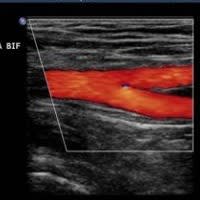

✓ Detection of PAD using Ultrasound

Peripheral arterial disease is from a narrowing or stenosis of the arteries which supply oxygenated blood to the legs. This is mainly caused by disease in the wall of arteries known as atheroma, which develops gradually over a length of time. It begins with cholesterol from the blood being deposited within the wall of arteries, leading to the thickening of the artery wall. This results in a narrowing or stenosis of the artery and a reduction of oxygenated blood flow to the leg.